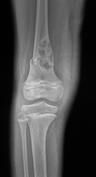

Dev Hücreli Kemik Tümörü

Kemiğin selim-agresif tümörü olarak kabul edilir. Genç erişkinde osteolitik karakterde kemik tümörüdür. Uzun kemiklerin ekleme yakın uç kısmından çıkabilir. Hastalar tümör bölgesinde devamlı ve giderek artan inatçı bir ağrı ve şişlik ile başvururlar.Sadece küretaj yapılan hastalarda yüksek lokal nüks yanında akciğer metastazı yapma potansiyeli olduğundan lokal agresif tümör olarak kabul edilir. Ama bu metastazlar ölümcül değildir.Diz eklemi en sık tutulan bölgedir. Diğer sık tutulan bölge el bileğidir. Kemik korteksini harap ederek yumuşak dokulara yayılım gösterebilir. Tanı için biyopsi şarttır. Brown tümörü ile ayırıcı tanısı yapılmalıdır. Tanı esnasında akciğer tomografisi çekilmelidir.

Tedavide genişletilmiş küretaj ve adjuvan ajanlarla kalan tümör hücreleri öldürülmeye çalışılır. Adjuvan ajan olarak; sıvı azot, alkol, fenol, argon koter, kriyoterapi, yüksek hızlı burr ve sementleme (kemik çimentosu) uygulanır. Eklemin tutulduğu vakalarda eklem feda edilir,protez veya artrodez uygulanabilir. Rezeksiyonun zor olduğu olgularda denosumab kullanılması önerilmektedir.Hastaların lokal nüks ihtimaline karşı 10 yıl süre ile takibi yapılmalıdır.